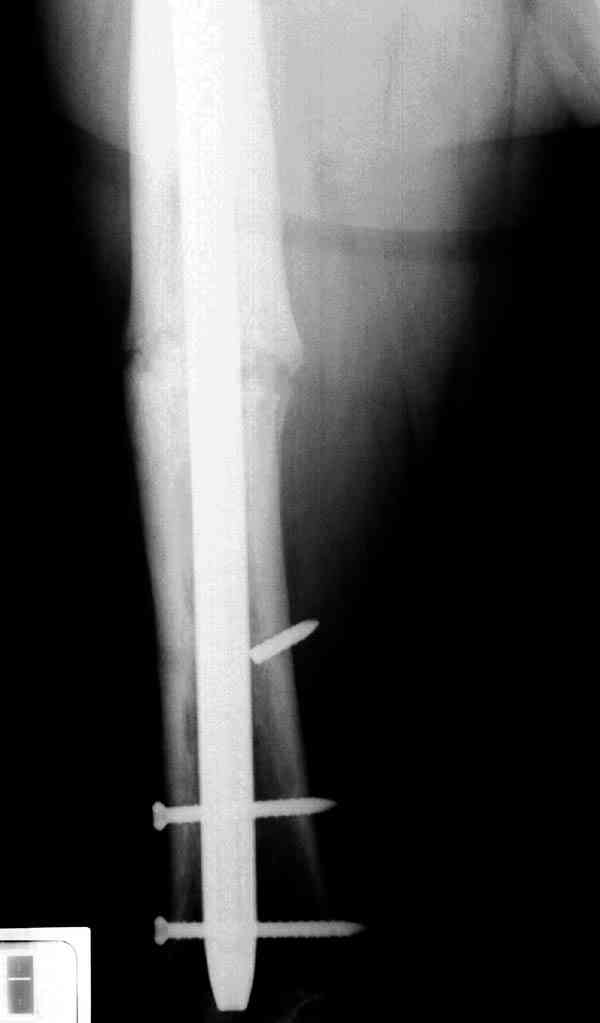

Уважаемые коллеги! У пациента 50-ти лет ложный сустав голени, перелом интрамедуллярного штифта. Перелому около 2 лет, ходить с полной нагрузкой начал через 3 мес. после операции. Боли при ходьбе почувствовал около 2 мес. назад. На данный момент ходит с полной нагрузкой без посторонней опоры. Среди коллег развернулась дискуссия по поводу способа оперативного лечения: -удаление штифта с перештифтовыванием блокированным штифтом с рассверливанием и остеотомией м\б кости -стабилизация зоны ложного сустава по медиальной поверхности LCP-пластиной с декортикацией или без -удаление штифта или без и синтез в АВФ с декотрикацией или без и остеотомией м\б кости

уважаемый коллега! Здесь имеется типичный тугой ложный сустав б/берцовой кости. У нас бы удалили старый стержень, реостеосинтез более толстым стержнем с рассверливанием с блокированием в динамическом варианте. Проблема будет с удалением дистального отломка стержня. Здесь на форуме это вопрос уже рассматривался неоднократно. Поищите по поисковику.Вот здесь, кажется http://weborto.net/forum/1164105478/, http://weborto.net/forum/1192794837

Все перечисленные варианты способны привести к желаемому результату. Несращение здесь - результат нестабильности, так что любой вариант

стабилизации решит проблему. Одного безоговорочно лучшего нет, у всех есть плюсы-минусы.

Наименьший по инвазивности - наложение спицевого аппарата без удаления стержня, с последующей либо дистракцией либо компрессией. Можно и устранить антекурвацию, это тоже создаст стабилизирующее напряжение тканей.

Наиболее быстро достичь опорности без боли и внешних приспособлений - удаление и блокируемый реостеосинтез с рассверливанием. Лучше бы тоже с

восстановлением оси (отклоняющая спица в дистальном отломке, чтобы новый стержень прошел не в старый канал, а кзади от него), еще и для создания дополнительного напряжения тканей в области несращения. Открывать зону несращения не надо.

Сросшаяся малоберцовая как распорка привела к образованию ложного сустава. В таких случаях удаляем сломанный штифт и проводим стимуляцию ложного сустава рассверливанием. Рассверливание канала создает стимуляцию на месте ложного сустава, и динамический вариант блокировки штифта с большим диаметром создаст стабильность. Ранняя нагрузка после остеотомии малоберцовой приведет к сращению ложного сустава.